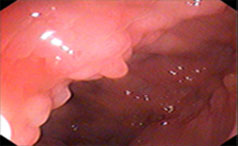

常见症状:腹痛、腹泻、便秘

左下腹或小腹部出现隐痛或绞痛

莫以病小而不防—浅谈胃肠息肉,牡丹江附大胃肠病医院【官网预约挂号:13206882659(微同号)】胃肠息肉,是消化科的常见疾病,许多做过胃......【详情】

常见症状:上腹隐痛、腹胀、不适

无痛性便血、脱垂